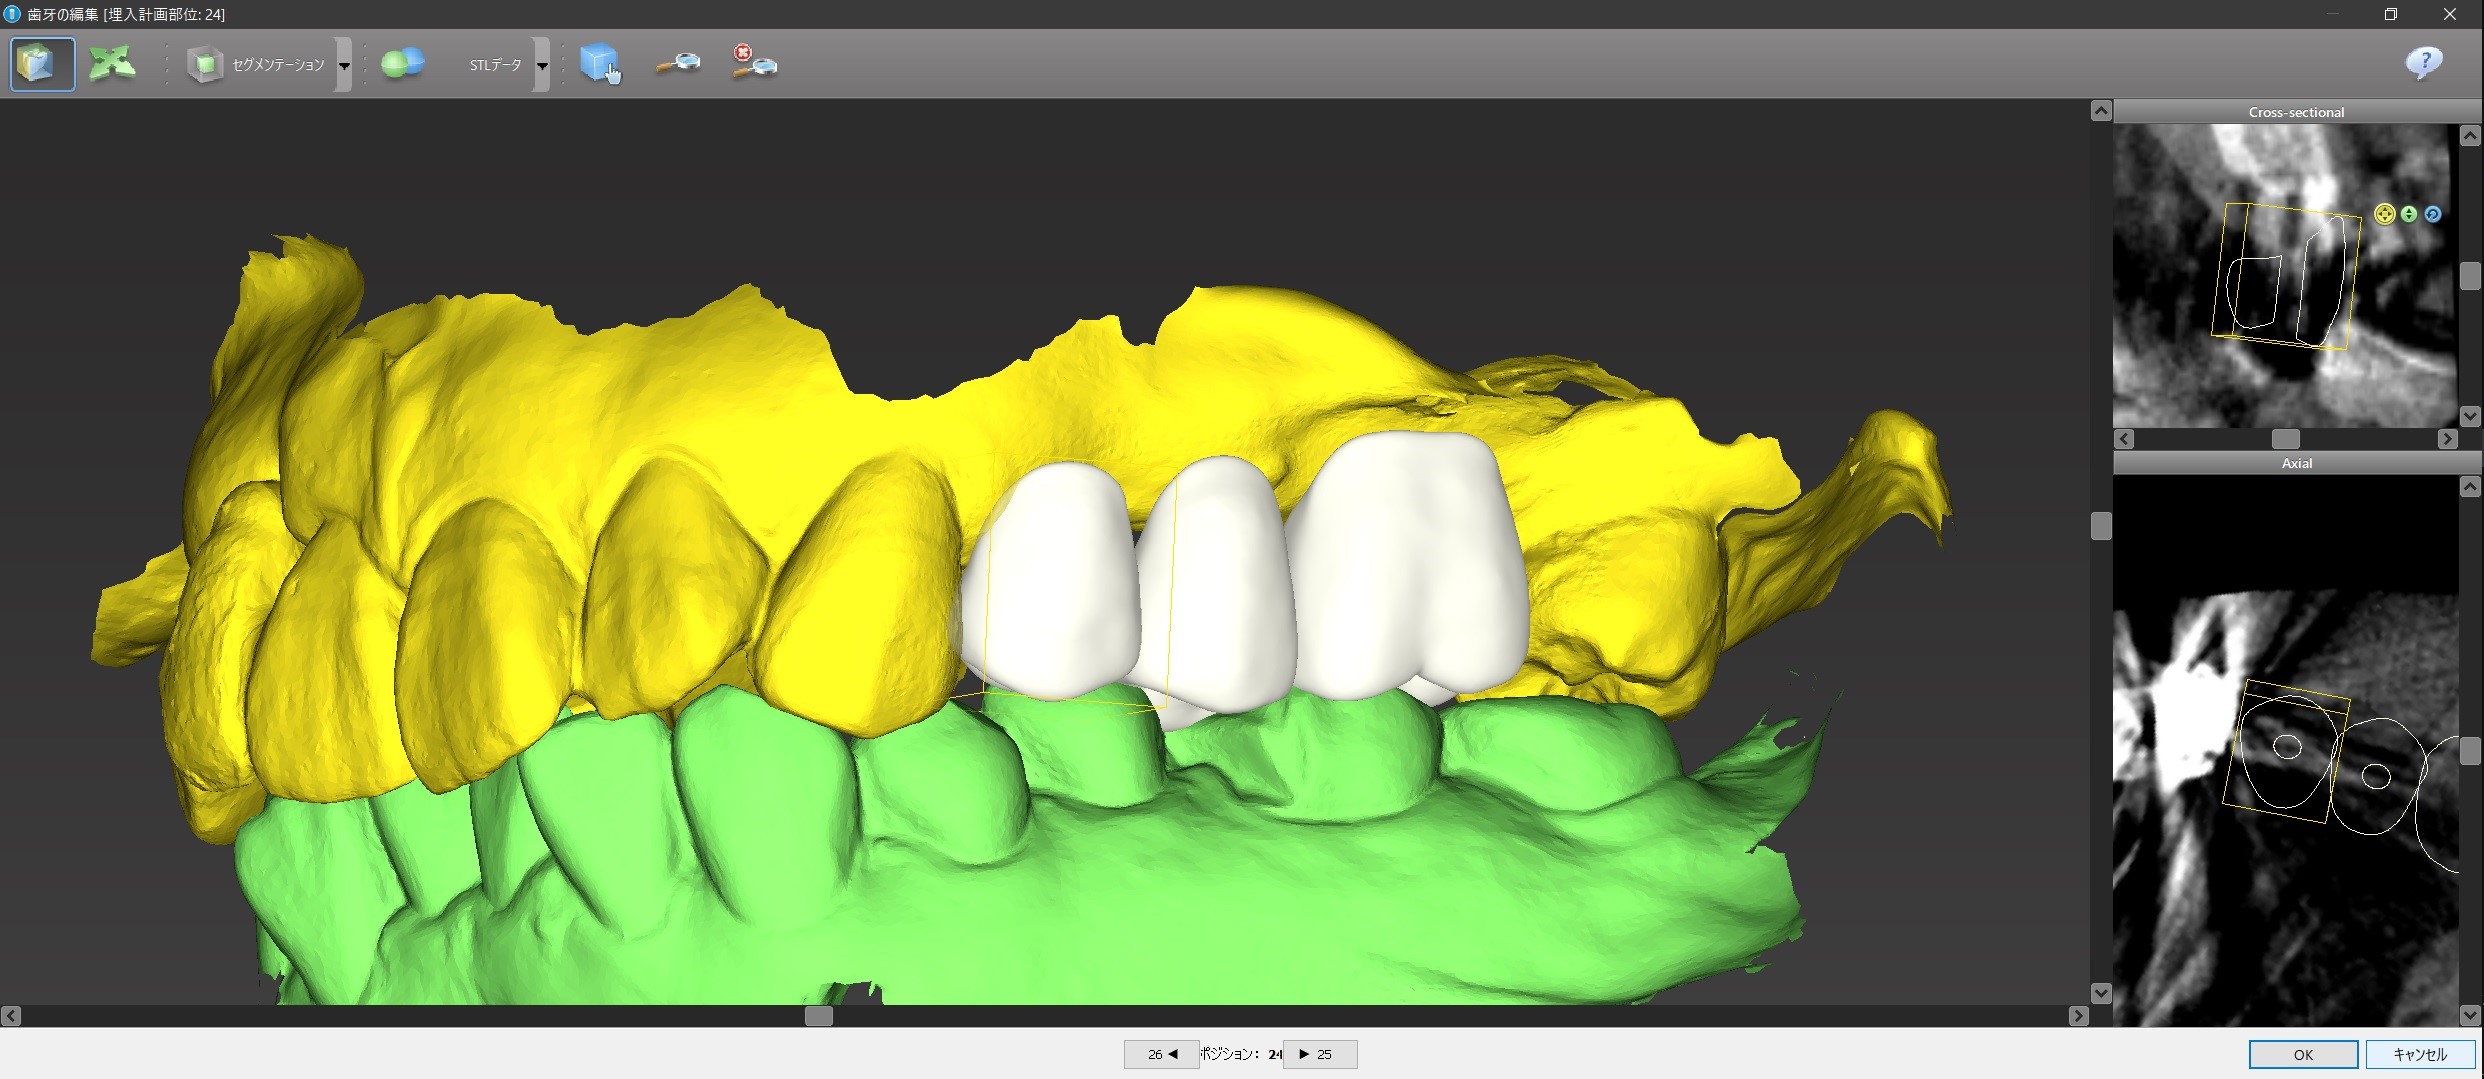

上下の歯のかみ合わせが分かりやすいように、CTの骨のデータの表示を消してバーチャル・ティースをカスタマイズします。

コンピュータ画面上で、下から見たり、裏から見たり、どアップで見て細かい調整をすることができます。

このように、まず先に上部構造の位置をシュミレーションするのです。

先に骨があるところにインプラントを入れて、それから上部構造を作っては、上部構造が上下のかみ合わせが悪いところに来てしまっても手遅れだからです。